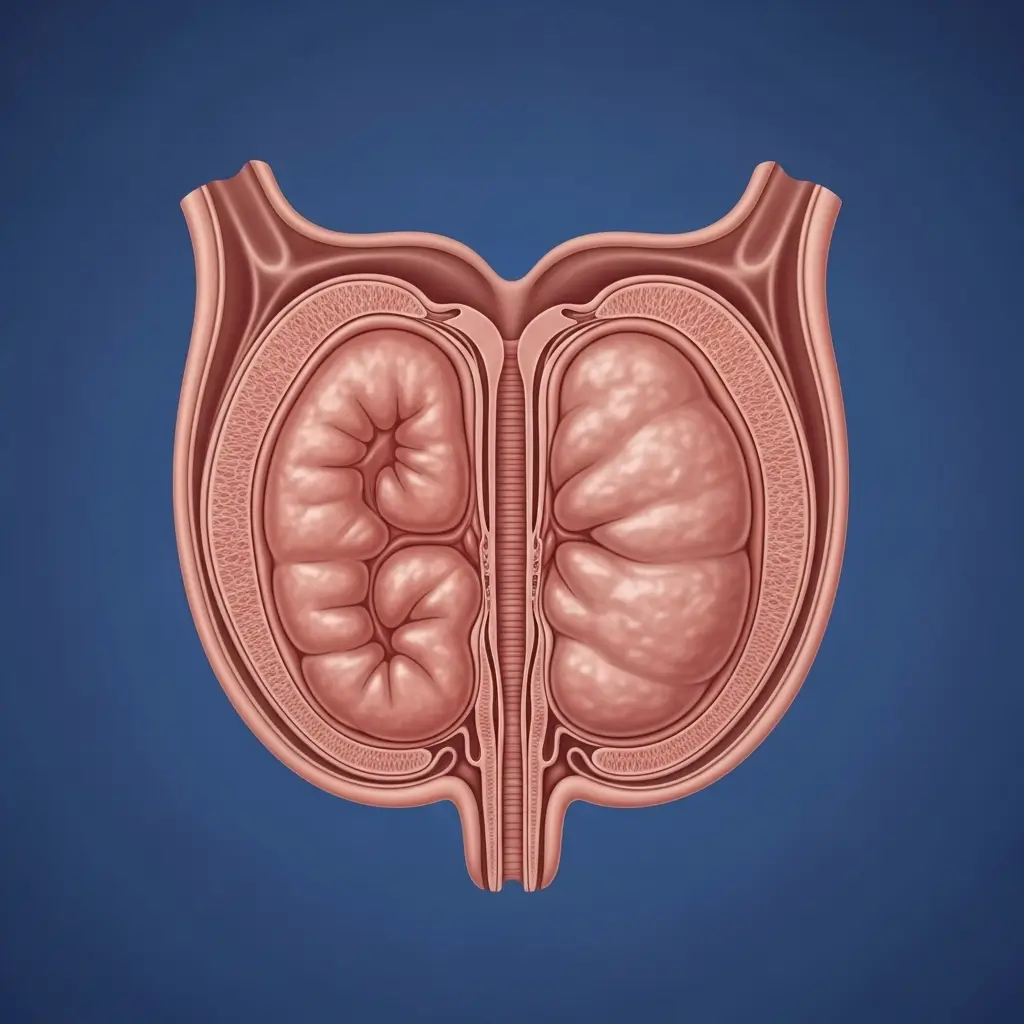

KIDNEY FAILURE

"Trapped" urine contaminates kidneys with toxins, causing TOTAL ORGAN FAILURE